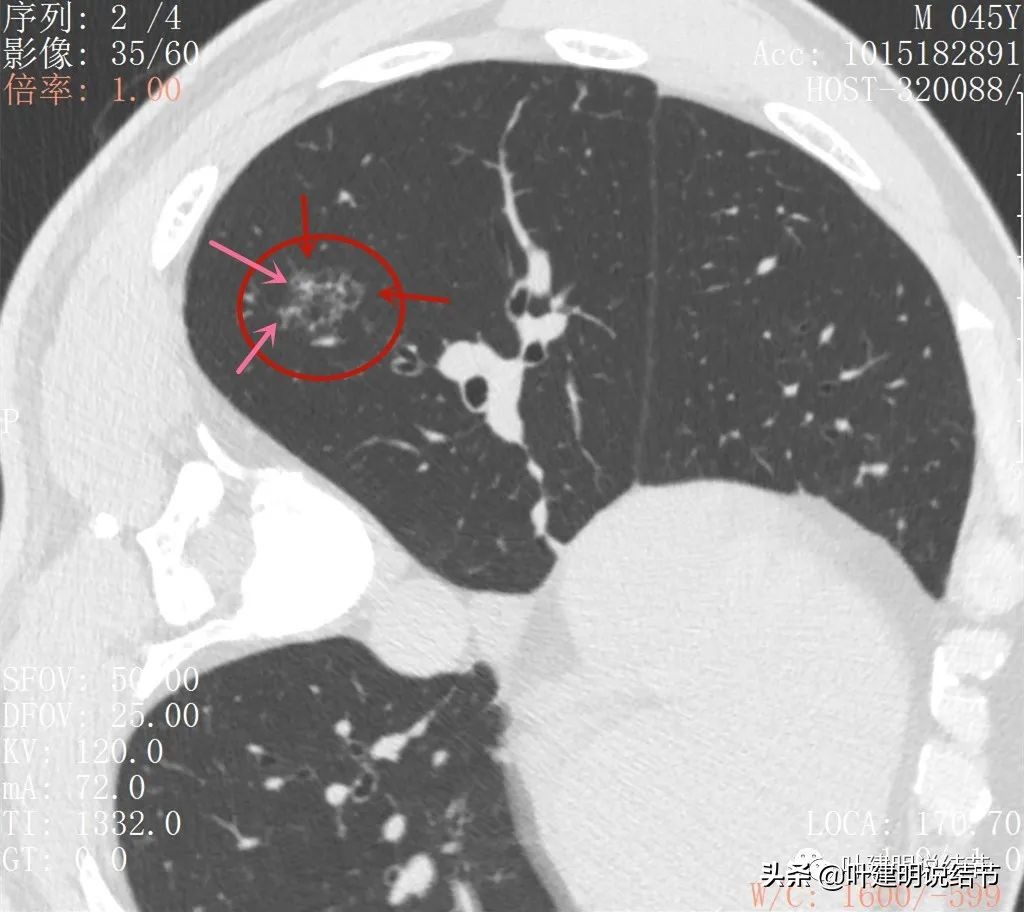

2022年5月复查靶扫描的图像:

病灶出现,磨玻璃密度,非圆形或类圆形,感觉比较散

病灶虽然不密,但轮廓较清,磨玻璃成分明显,感觉偏向恶性

病灶有少许实性成分(粉色箭头)

病灶似有血管进入(桔色箭头),而且血管异常增粗,整体病灶轮廓较清,似有分叶,中间有空泡征呈蜂窝状

病灶内部见血管穿行,轮廓与瘤肺边界清楚

扩张的细支气管感觉较为僵硬

少许区域有密度较高的部分,扩张细支气管明显,且显僵硬